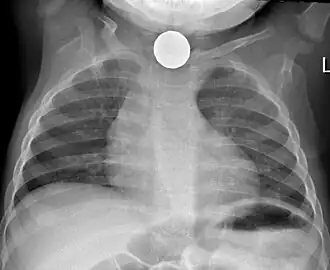

Tension pneumothorax

Tension pneumothorax is an emergent condition in which air gets trapped in the space between the chest wall and the lung. This space is referred to as the pleural space. Because air can't escape from this space, the air pocket grows larger and larger, resulting in the lung collapse closest to the pneumothorax. Forces are transmitted to the mediastinum and effectively "push" the mediastinal structures to the opposite side of the chest.[5]